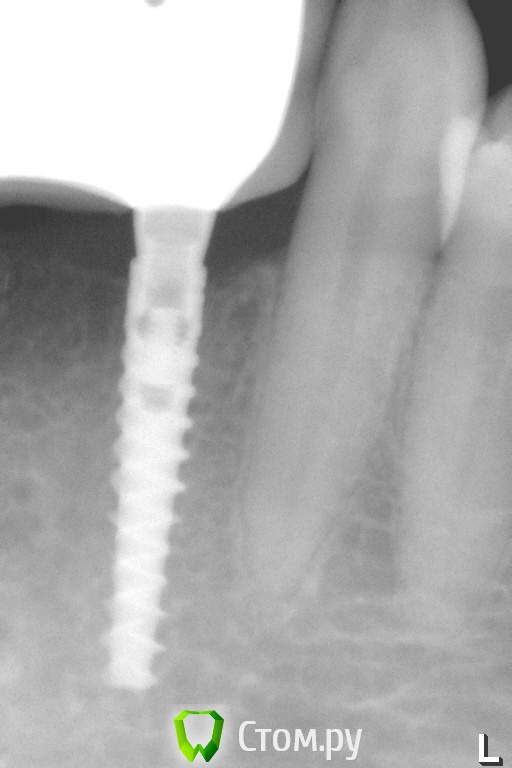

Pavel-Pskov Опубликовано 17 апреля, 2014 Поделиться Опубликовано 17 апреля, 2014 Есть несколько работ на узких имплантах 3.0 мм . Тоже маленько кость наросла. 3 Ссылка на комментарий

Pavel-Pskov Опубликовано 18 апреля, 2014 Автор Поделиться Опубликовано 18 апреля, 2014 А какой срок наблюдения?Два года. Ссылка на комментарий

Pavel-Pskov Опубликовано 18 апреля, 2014 Автор Поделиться Опубликовано 18 апреля, 2014 Присоединяюсь к вопросу. Интересна первичная ситуация: какова ширина была?5-6 мм. Одномоментно с удалением. 41 и 31 были вообще не в кости 42 и 32 где то на 2-3 мм. Ссылка на комментарий

Pavel-Pskov Опубликовано 18 апреля, 2014 Автор Поделиться Опубликовано 18 апреля, 2014 альфа био ченджибл?ADIN NP. Сейчас еще интереснее тройки есть, пока наблюдаю. Ссылка на комментарий

Pavel-Pskov Опубликовано 18 апреля, 2014 Автор Поделиться Опубликовано 18 апреля, 2014 Разделом промахнулись.Я бы сказал - кость не наросла, кость не ушла после субкрестальной установкиНа RG где один имплант год назад , где два сейчас. Небольшая разница есть по моему. Ссылка на комментарий